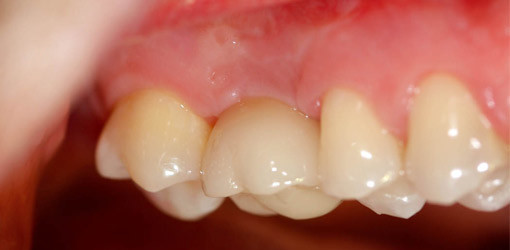

Die fertigen Abutments haben eine vorgefertigte Passform entsprechend der implantatdurchmesserkongruenten Titanbasis, um eine eineindeutige Reposition entsprechend des Scans zu gewährleisten. Dieser Aufbau wird mit Panavia F 2.0 auf die Titanbasis geklebt (Abb. 8–9). Der Vorgang erfolgt außerhalb des Mundes, um die Klebereste kontrolliert entfernen zu können, ohne das empfindliche Sulkus­epithel zu traumatisieren. Die eingegliederte Mesostruktur stützt die Gingiva optimal und legt den Kronenrand in klinisch kontrollierbare Bereiche (Abb. 10, 11a, 11b).

Bei dem zweiten vorgestellten klinischen Fall handelt es sich um eine implanto­logisch prothetische Rehabi­litation einer 45-jährigen Patientin, die sich erstmals im Februar 2009 vorstellte. Als Ausgangssituation imponierten die mittleren, endodontisch behandelten Oberkieferinzisivi mit ex-tremer Protrusion, die nach eingehender klinischer und röntgenologischer Untersuchung als nicht mehr erhaltungswürdig eingestuft wurden (Abb. 12). Nach ausführlicher Beratung mit Wax-up entschied sich die Patientin für die Implantation Regio 11 und 21. Am 12.02.09 wur­den schablonengeführt zwei alphatech Bonitex Implantate 3,8/16 inseriert, welche nach acht Wochen mit Langzeitprovisorien versorgt wurden. Im Dezember 2009 ist die endgültige keramische Restauration mit individuell gefertigten Zir­konoxidabutments und Keramikkronen sowie Veneers auf 12 und 22 einge­gliedert worden (Abb. 13–19).